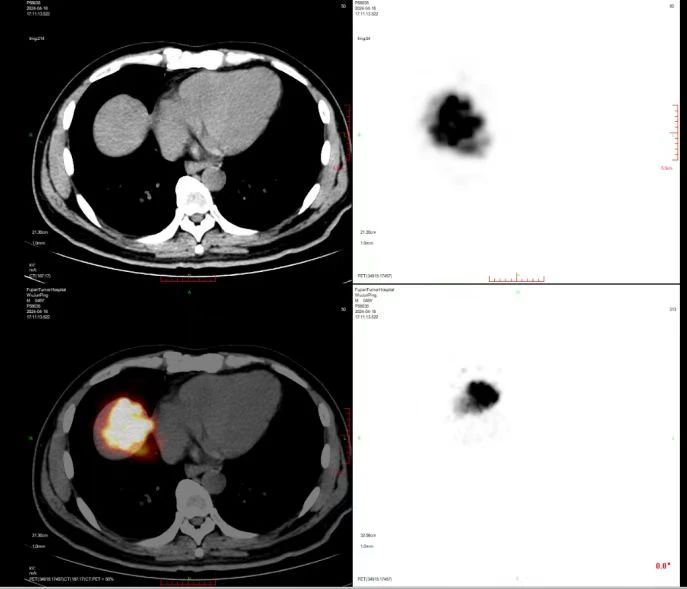

术后即时PET-CT显示钇90放射性微球完全分布在肿瘤内,正常肝实质未受影响